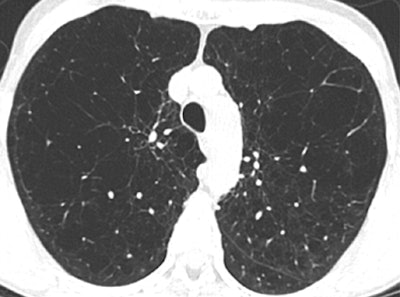

| Axial CT scans in two subjects with different COPD phenotypes: emphysema-predominant COPD (≥ 35% emphysema, <1.75-mm segmental bronchial wall thickness) (above) and airway-predominant COPD (<35% emphysema, ≥ 1.75-mm segmental bronchial wall thickness) (below). Images republished with permission of the Radiological Society of North America, from Radiology, July 25, 2011, 110173. |

In addition, while many patients had a mixture of structural changes related to their COPD, two subgroups predominantly with emphysema or large airway disease could be identified.

Patients with more than 35% emphysema volume and wall thickness greater than 1.75 mm had a higher COPD exacerbation frequency than did the subjects with less than 35% emphysema and a wall thickness of less than 1.75 mm.

The less-severe patients in both groups reported experiencing a mean of 0.62 exacerbation per year, compared with means of 1.1 exacerbations per year reported by the emphysema-predominant group (p < 0.0001) and 0.8 exacerbation per year reported by the airway-predominant group (p = 0.07).